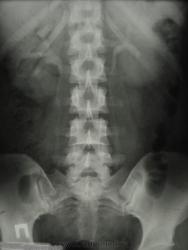

В наблюдении, похоже, имеются аберрантные внутрипочечные сосуды обеих почек; каликоэктазия (не врождённая же), больше справа, что служит основанием для дообследования больной (включая доплерографию сосудов почек...) Не факт, что гломерулонефрит единственный/правильный диагноз!..

3.Цель исследования при гломерулонефрите??? Хорошо, допустим у неё есть в почке(одной, как видно по этим снимкам) аберрантный сосуд. И что? Прожила она с ним 18 лет и ничего, а утверждать, что он(сосуд) как-то повлиял на возникновение гломерулонефрита - шаманизм.

4.Размеры ЧЛС нормальные.

3 и 4 - Гломерулонефрит - страдание паренхимы, каликоэктазия (убеждён, имеет место) "цветёт" не на пустом месте, при длительной задержке мочи в ЧЛС - страдает паренхима. Надеюсь, ход мысли понятен. А сосуды (и аберрантные) с возрастом изменяются - уплотнённые, ригидные нарушают отток мочи в большей степени...